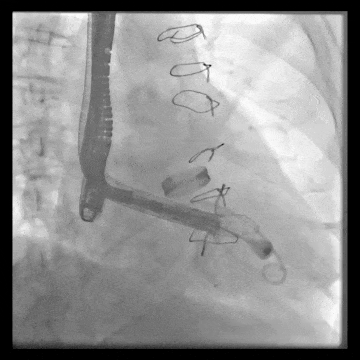

術(shù)后DSA、超聲顯示人工瓣膜穩(wěn)定性良好,瓣葉啟閉正常,無瓣周漏

術(shù)后DSA